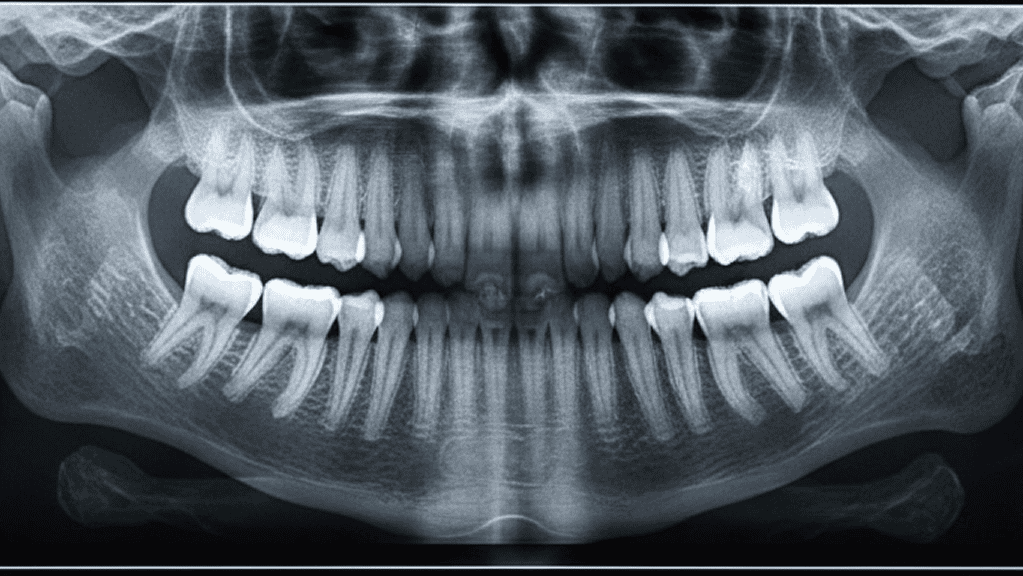

Röntgen liefert klare Bilder bei deutlich reduzierter Strahlenbelastung. Die Aufnahmen entstehen in Sekunden und sind sofort am Bildschirm sichtbar. Karies, Entzündungen oder versteckte Schäden werden präzise erfasst, bevor Beschwerden entstehen. Die digitale Verarbeitung ermöglicht eine exakte Diagnose und eine zielgerichtete Behandlung. Alle Daten lassen sich sicher archivieren und bei Bedarf schnell vergleichen, um Veränderungen früh zu erkennen.